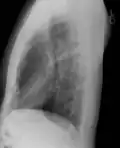

Обработанная цифровая рентгенограмма грудной клетки (лёгочные поля в позитивном изображении, с повышенной контрастностью). Рентгенограмма грудной клетки в боковой проекции.

Рентгенограмма грудной клетки в боковой проекции. Некачественная рентгенограмма грудной клетки.